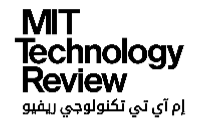

إن اختبار الأجنَّة للكشف عن مخاطر الأمراض -بما فيها مخاطر الأمراض التي لا تحدث سوى في وقت متأخر من الحياة- يعتبر مقبولاً من الناحية الأخلاقية من قِبل أطباء الخصوبة في الولايات المتحدة، لكن نماذج درجات الحمض النووي الجديدة تعني أن الآباء قد يتمكنون من اختيار أطفالهم اعتماداً على بعض الصفات مثل معدل الذكاء أو وزنهم وهم كبار، ويعود ذلك إلى أن هذه الصفات -مثل مرض السكري من النوع الأول- هي نتيجة لتأثيرات جينية معقدة، والتي صُمِّمت خوارزميات التنبؤ لإيجادها.

تقول ميشيل ماير (المتخصصة في الأخلاقيات الحيوية في مؤسسة جايسينجر هيلث سيستم (Geisinger Health System) التي تحلل المشاكل المتعلقة بالوراثة التكاثرية): "إنه أمر صغير، ولكن له عواقب كبيرة؛ لأنه إذا كان يتم إجراء ذلك من أجل شيء أكثر خطورة، فسيكون من السهل جداً البحث عن أي شيء آخر؛ فهذا هو ملف الجينوم الخاص بكل جنين، وما عليك سوى البحث في صفحاته"، فتخيَّل إمكانية اختيار أن يرتاد الجنين جامعة هارفارد مثل أمه، أو يكون طويل القامة مثل أبيه.

قامت شركة جينوميك بريديكشن في العام الماضي بحجز مكان للعرض في الاجتماع السنوي للجمعية الأميركية للطب التناسلي، وكانت الجمعية -التي تمثِّل أطباء وعلماء الخصوبة- قد ذكرت من قبل أنها تعتقد أن اختبارات الأجنة للكشف عن الأمراض التي تحدث في وقت متأخر من الحياة -مثل مرض الزهايمر- ستكون "مبررة أخلاقياً"، وقد ذكرت "الحرية الإنجابية" للآباء من بين الأسباب لذلك.

وكانت الجمعية أكثر تردداً حول اختيار جنس الأجنة (وهو أمر تسمح به اختبارات التشخيص التقليدية)، وتركت الأمر لتقدير الأطباء، ويبدو أن مواقف الجمعية مجتمعة تفتح الباب لأي نوع من القياسات، طالما أن الاختبار مبرر لسبب طبي.